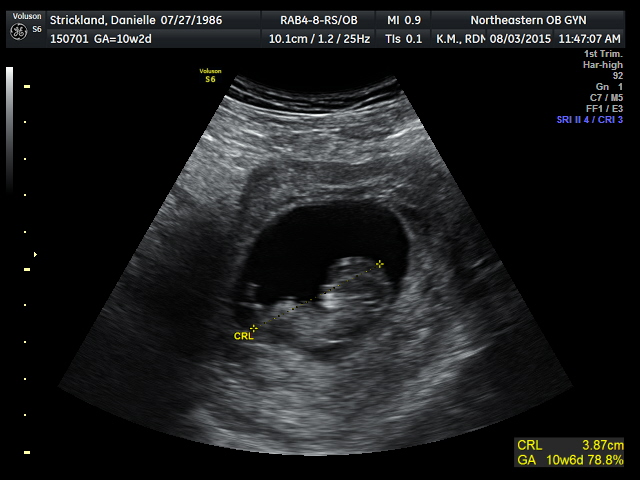

10w2d today! Baby measuring a few days ahead, I blame that on his/her dad's giant self. FHR was 184, crazy to see how fast it was, but after my h/o MC, I'll definitely take a fast HR!